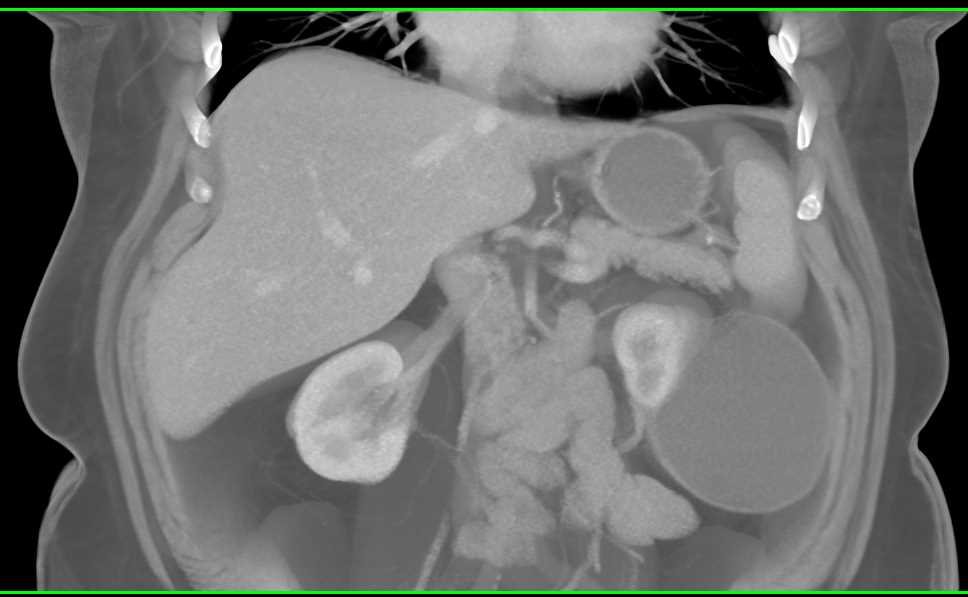

High Density Renal Cyst